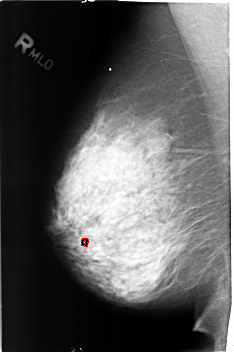

B_3175_1.RIGHT_MLO

FILE: B_3175_1.RIGHT_MLO.OVERLAY

TOTAL_ABNORMALITIES 1

ABNORMALITY 1

LESION_TYPE CALCIFICATION TYPE LUCENT_CENTER DISTRIBUTION N/A

ASSESSMENT 2

SUBTLETY 3

PATHOLOGY BENIGN_WITHOUT_CALLBACK